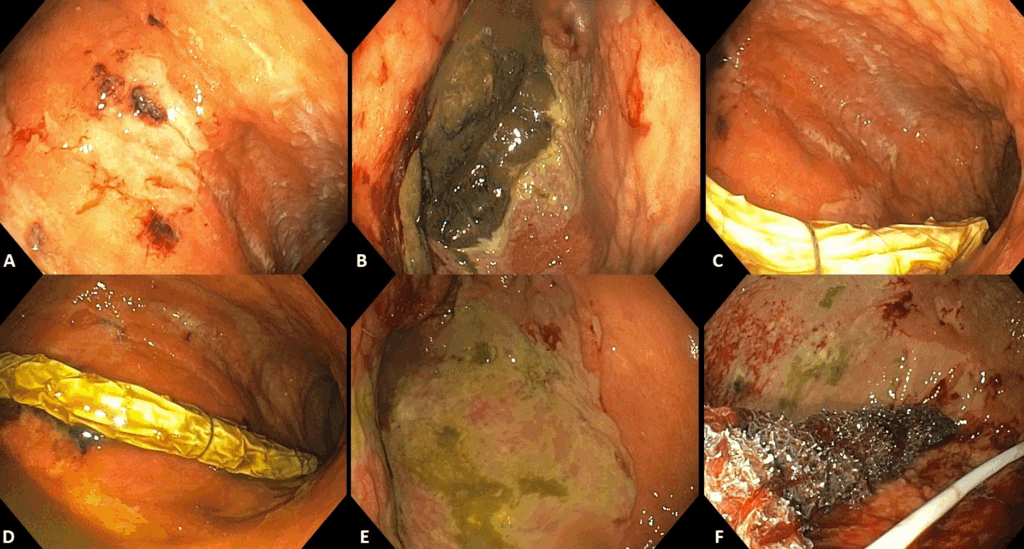

- El TEV se cambió semanalmente durante 21 días (figuras 2 y 3).

- Se observó resolución completa de las áreas de necrosis y ulceración (figuras 2 y 3).

Figura 4. Adaptado de Dall’Agnol et al. (9):

A-C: 21 días de TEV

D-F: 1 semana después de la finalización de la TEV